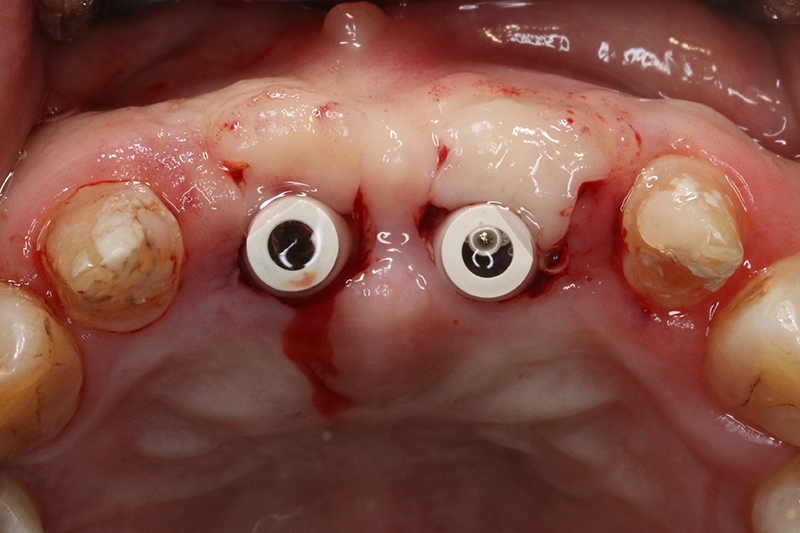

接續牙周治療完成後的療程,上排門牙植牙的問題處理,長期不斷的發炎化膿流血,除了造成周圍組織發炎與牙齦腫脹,同時造成齒槽骨被細菌破壞與吸收,根本解決的方式是建議移除感染與位置不佳的植體,先進行植牙移除手術+齒槽骨保存術,先使用膠原蛋白促進軟組織癒合,加快癒合的速度。

可見植體移除後骨缺損範圍大

取出的舊有one piece植體,舊式植體。